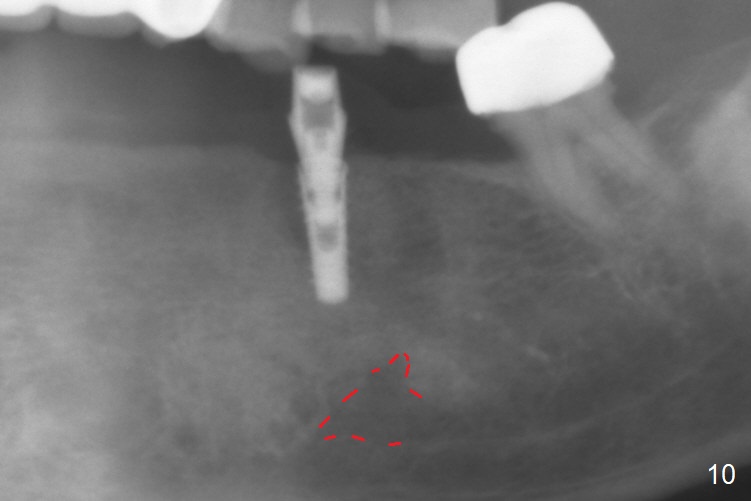

After removal of the pontic at #19 and retainer at #20 (Fig.1) and of vertically fractured root, the buccal plate is found to be defective (Fig.2 *). An implant will be placed as lingual as possible. Since the apex of the affected tooth is coronal to the Mental Loop (Fig.3 red dashed line), an osteotomy (Fig.4 yellow arrow) to be established in the mesial slope (blue dashed line) after extraction (black area) appears to be safer than that along the long axis of the tooth. The initial osteotomy is accomplished by free hand (Fig.5), but when the lower RPD is inserted, the superior end of the 1.5 mm pilot drill is distal (Fig.6). When the trajectory is corrected using the RPD as a surgical guide at the same depth (17 mm gingival level), brisk hemorrhage is from the osteotomy without severe pain. After hemostasis is achieved by packing the socket with Osteogen plug and bone graft and packing bone graft into the osteotomy, 3.3 mm Magic Drill is used for 14 mm. A 4x11 mm IBS implant is placed with 60 Ncm (Fig.7). The implant is then placed deeper, followed by placement of a 4.5x4(3) mm abutment and further bone graft (Fig.8). Finally the implant/abutment complex is apparently in an acceptable mesiodistal position with a large buccal gap which has been filled by bone graft (Fig.9 *). In fact the Mental Loop seems to have been not violated in the procedure (Fig.10). X-ray is taken 3 and 6 months postop. Bone graft (Fig.11,12 (CBCT) *) appears to remain over the buccal (B) surface of the implant coronally 13 months postop (7 months post cementation). The gingiva at #19 and 20 is apparently healthy 8 months post cementation except mild recession at #20 (Fig.13).